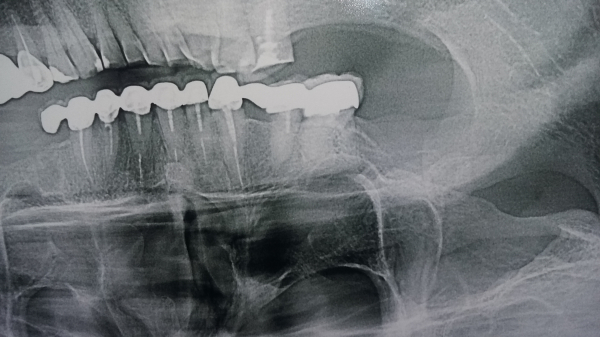

Прикрепленые фото

По данному рентгеновскому снимку практически все корневые каналы зубов, пролечены некачественно, и определить какой именно зуб вызывает подобные жалобы дистанционно невозможно. Необходим осмотр и компьютерная томография. Проконсультируйтесь очно с опытным врачом-стоматологом.